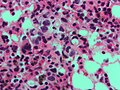

Blue & pink

H&E is the standard...

- Too much PINK = DEAD (necrosis).

- Too much BLUE = BAD.

- Blue is bad and pink is dead![1]